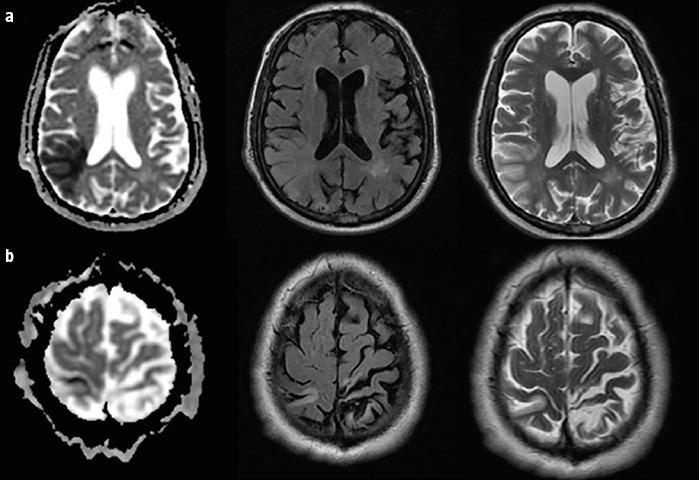

Four patients presented after sudden-onset gait lateropulsion. On neurological examination, all patients had at least one cortical sensory deficit and wide-based gait with lateropulsion towards the side of the cortical deficit. Neuroimaging revealed a subacute parietal lobe stroke contralateral to the side of gait lateropulsion. In two patients we found bilateral lateropulsion with predominance towards the side of cortical deficit and increase of unsteadiness with eye closure (an apparent Romberg sign), with neuroimaging revealing bilateral parietal strokes (subacute contralateral and chronic ipsilateral to gait lateropulsion).

4 例患者出现突发性步态侧方偏倚。在神经学检查中,所有患者均至少存在一处皮质感觉缺失和宽基底步态,并伴有向皮质缺失侧的侧方偏倚。神经影像学显示与步态侧方偏倚侧相对应的亚急性顶叶中风。在 2 例患者中,我们发现双侧侧方偏倚,以皮质缺失侧为主,并伴有闭眼时不稳定性增加(明显的 Romberg 征),神经影像学显示双侧顶叶中风(亚急性对侧和慢性同侧与步态侧方偏倚)。